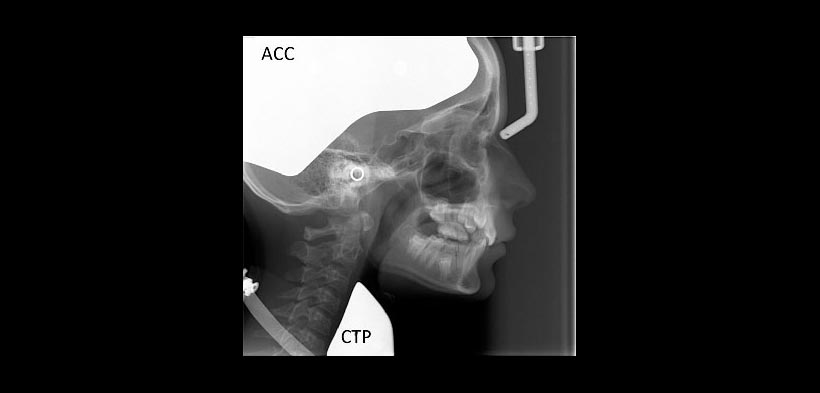

Recientemente, el colimador craneal anatómico (ACC) (ver figura 1), se introdujo para proteger la zona craneal y base del cráneo de la radiación. Esta zona craneal no tiene información de diagnóstico para el ortodoncista. Otra área que está en el campo de visión de las radiografías laterales sin información de diagnóstico es la región de la tiroides. La glándula tiroides es uno de los órganos más radiosensible en la región de la cabeza y el cuello. Las directrices europeas y norteamericanas indican que el uso e protectores tiroideos deben ser de carácter obligatorio para los niños y en los adultos siempre y cuando la zona de la tiroides no va a interferir con el examen.

Los protectores cefalométricos de tiroides (TCP) (ver figura 1), para proteger a la glándula tiroides durante la toma de una radiografía lateral se introdujeron por primera vez por Block en 1977 y están fácilmente disponibles. Sin embargo algunos exámenes hechos en la radiografía lateral utilizan las vértebras como indicadores de madurez esquelética (SMI), por lo cual es necesario que estos protectores protejan a la tiroides pero sin oscurecer la zona cervical.

Figura 1. Utilización del colimador craneal anatómico (ACC) y del protector tiroideo cefalométrico (CTP) antes de la exposición de una radiografía lateral.

Figura 2. Radiografía lateral obtenida mediante el uso del protector craneal y protector tiroideo, nótese que no interfieren con ninguna estructura anatómico con valor diagnóstico.